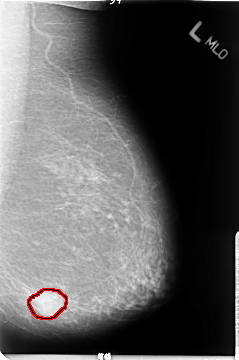

B_3049_1.LEFT_MLO

FILE: B_3049_1.LEFT_MLO.OVERLAY

TOTAL_ABNORMALITIES 1

ABNORMALITY 1

LESION_TYPE MASS SHAPE IRREGULAR MARGINS ILL_DEFINED

ASSESSMENT 4

SUBTLETY 5

PATHOLOGY MALIGNANT

TOTAL_OUTLINES 1

BOUNDARY